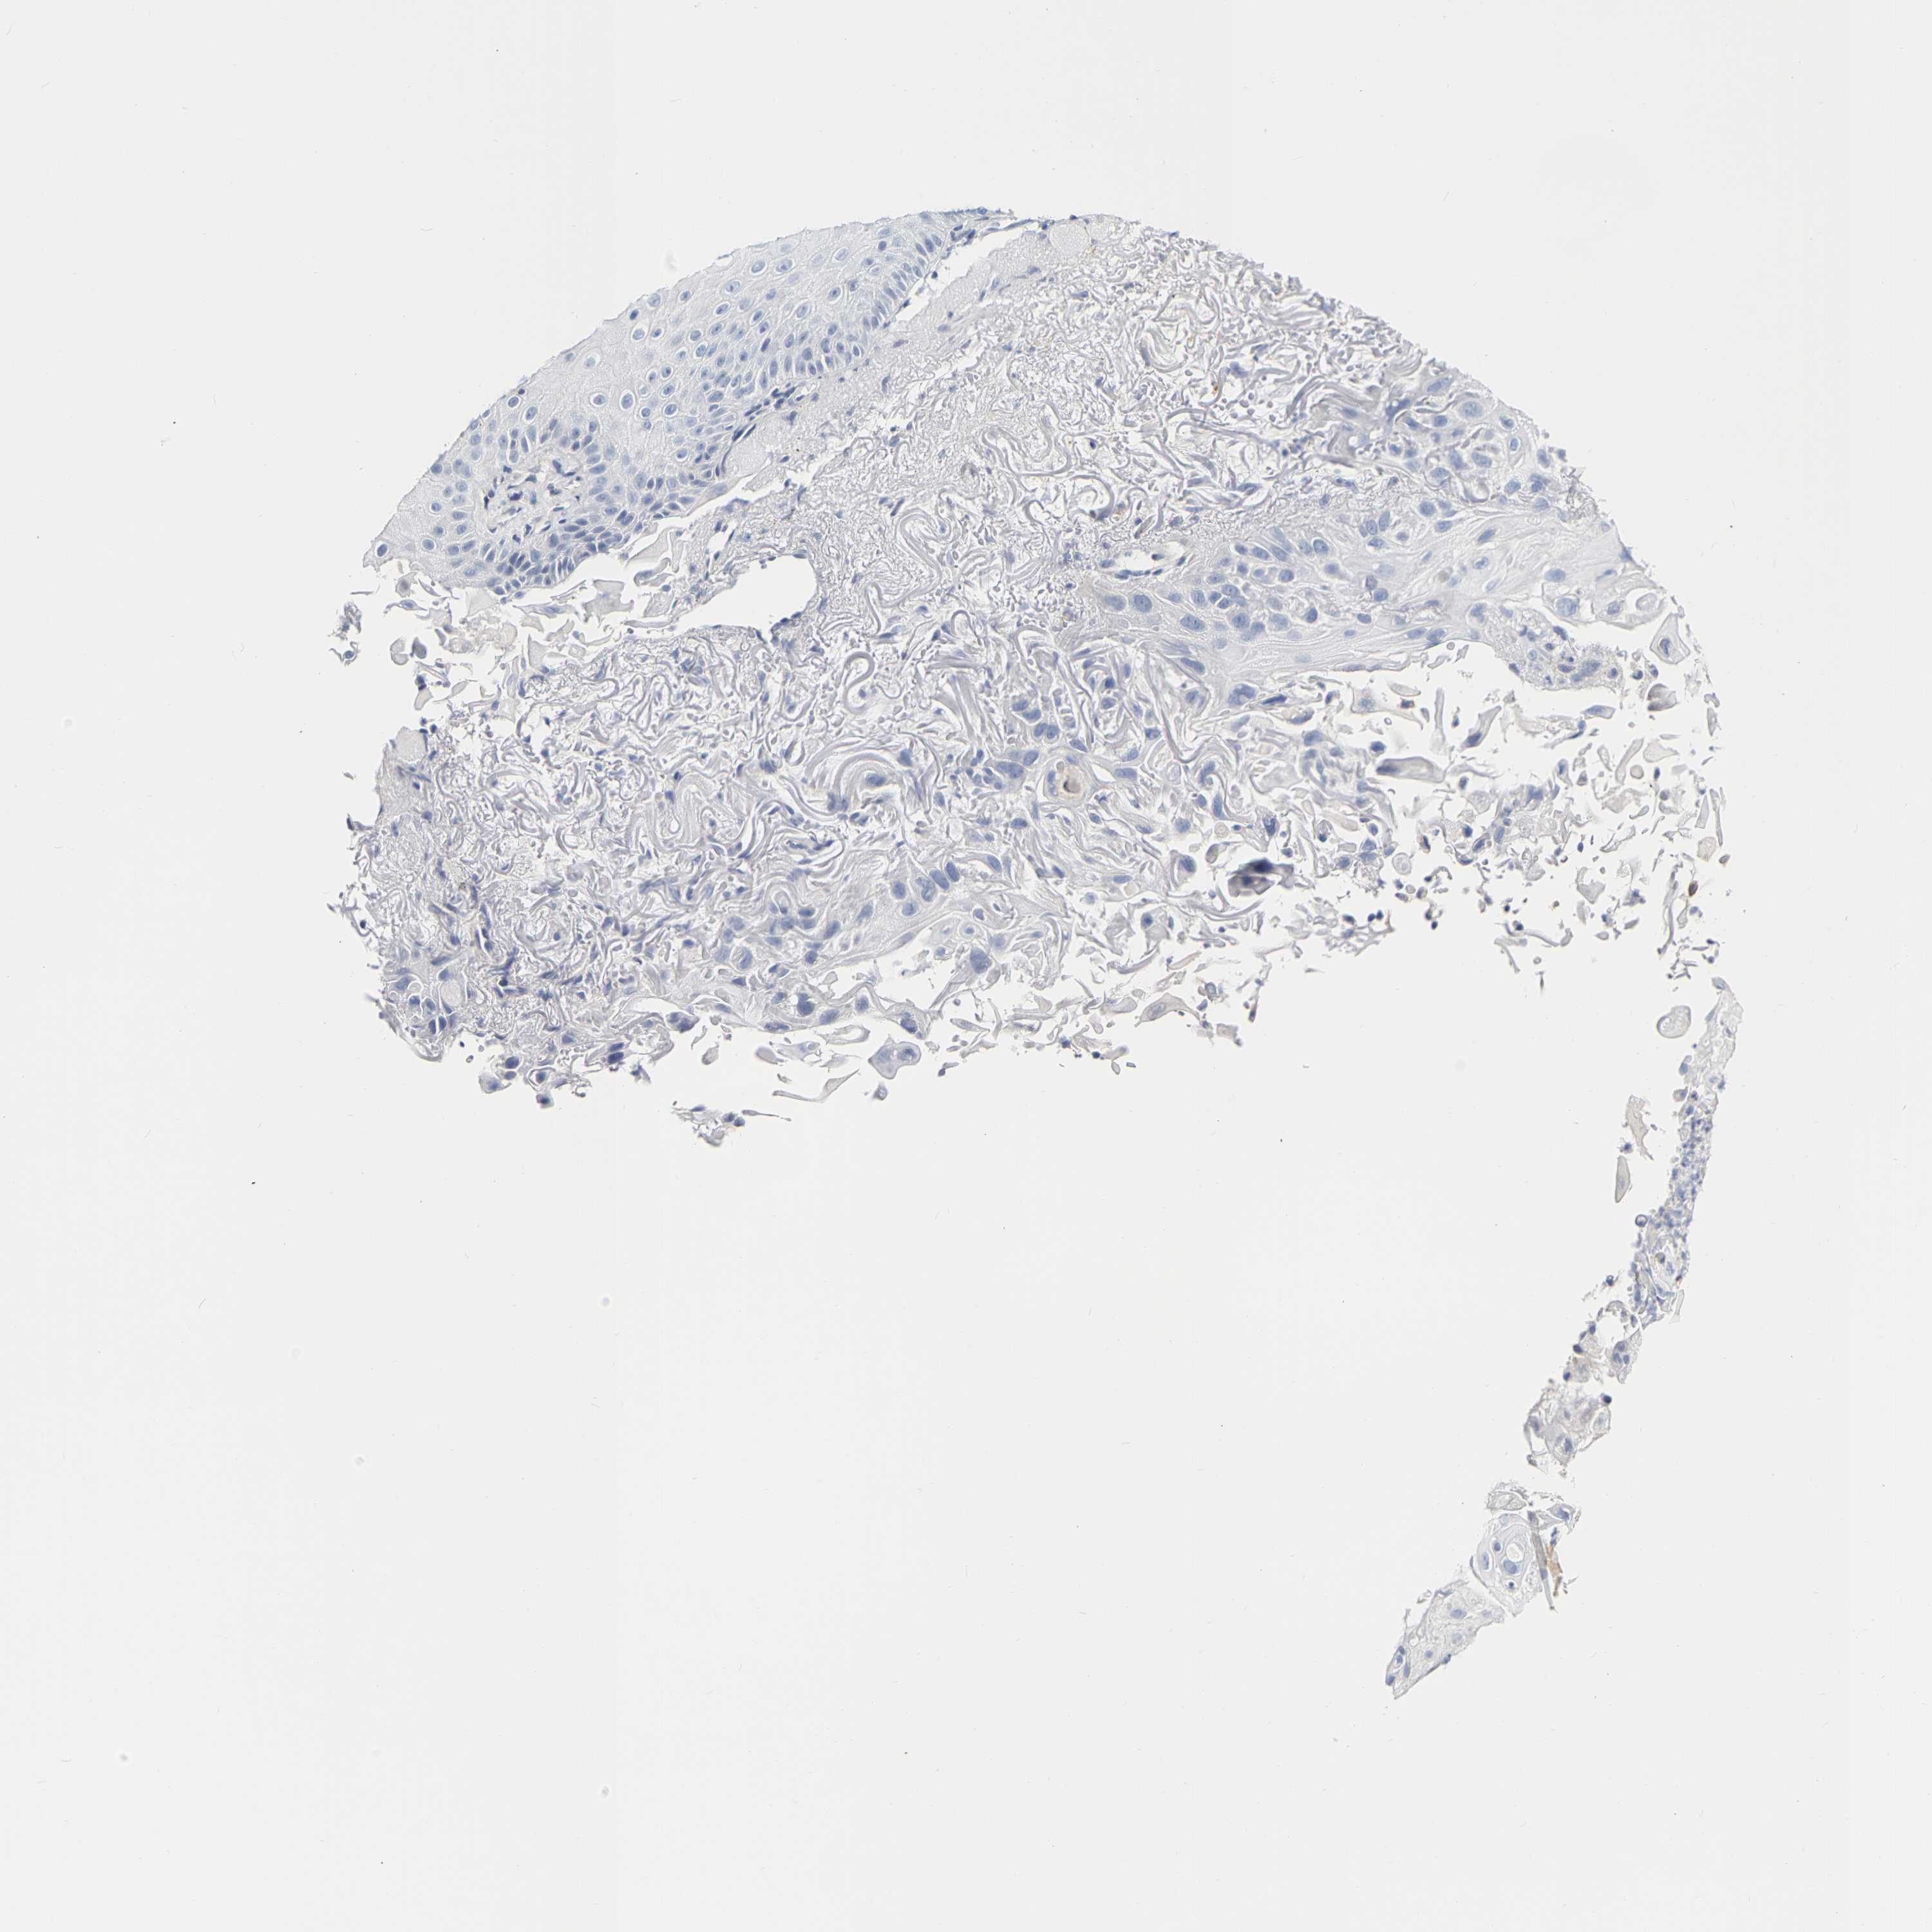

SKIN CANCER - Protein expressioni

A mouse-over function shows sample information and annotation data. Click on an image to view it in a full screen mode. Samples can be filtered based on level of antibody staining by selecting one or several of the following categories: high, medium, low and not detected. The assay and annotation is described here.

Each image is clickable and will lead to virtual microscopy that enables deeper exploration of all samples and also displays staining intensity scores, fraction scores and subcellular localization as well as patient and tissue information for each sample.

Antibody HPA028386

Squamous cell carcinoma, metastatic, NOS